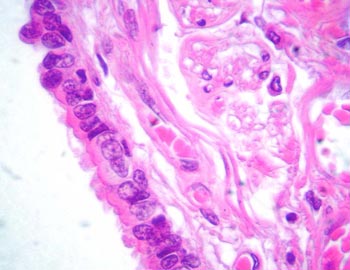

Visión específica: a mayor aumento podemos delimitar en la SG y de superficie a profundidad las tres capas arquitecturales: capa molecular o superficial, capa de las células de Purkinje o intermedia y capa de los granos cerebelosos o profunda. En íntimo contacto esta última nos encontramos con la SB, rica en fibras nerviosas y células gliales. En la capa molecular, en contacto con la superficie meníngea veremos escasas células neuronales y gliales con abundante neuropilo. La capa de células de Purkinje se distingue por los grandes somas piriformes neuronales de citoplasma eosinófilo y núcleo redondeado con nucleolo evidente que en ocasiones muestra la salida del gran tronco dendrítico en dirección a la capa superficial. La capa de los granos es densamente celular con elementos redondeados neuronales de pequeño tamaño con escaso neuropilo. Por último la sustancia blanca esta constituida por fibras nerviosas y celularidad escasa glial formando el eje de la laminilla y el tronco del cerebelo.

- Caracterizar los elementos celulares de la capa de las células de Purkinje.